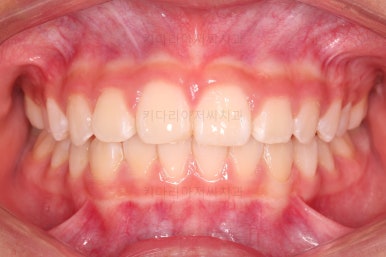

부산소아교정 마무리 사진입니다.

프리올소로 유지과정까지 총 2년 3개월 가량 걸렸고요.

이정도 마무리면 굳이 2차교정까지 안해도 되겠죠?

전후 비교해 볼게요.

웃을 때 보이는 느낌도 많이 좋아졌고요.

정교한 조절은 안했지만 치열이나 교합/맞물림 등 매우 좋아졌습니다.